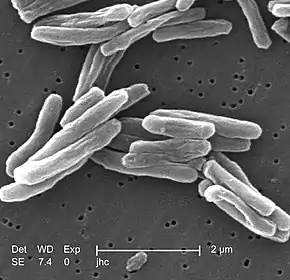

Extrapulmonary tuberculosis is tuberculosis (TB) within a location in the body other than the lungs. It accounts for an increasing fraction of active cases, from 20 to 40% according to published reports,[2] and causes other kinds of TB.[3][4] These are collectively denoted as "extrapulmonary tuberculosis".[4] Extrapulmonary TB occurs more commonly in immunosuppressed persons and young children. In those with HIV, this occurs in more than 50% of cases.[4] Notable extrapulmonary infection sites include the pleura (in tuberculous pleurisy), the central nervous system (in tuberculous meningitis), the lymphatic system (in scrofula of the neck), the genitourinary system (in urogenital tuberculosis), and the bones and joints (in Pott disease of the spine), among others.

Infection of the lymph nodes, known as tubercular lymphadenitis, is the most common extrapulmonary form of tuberculosis.[4][5] An ulcer originating from nearby infected lymph nodes may occur and is painless. It typically enlarges slowly and has an appearance of "wash leather".[6]

When it spreads to the bones, it is known as skeletal tuberculosis,[4] a form of osteomyelitis.[7] Tuberculosis has been present in humans since ancient times.[8]

A potentially more serious, widespread form of TB is called "disseminated tuberculosis", also known as miliary tuberculosis.[9] Miliary TB currently makes up about 10% of extrapulmonary cases.[10]